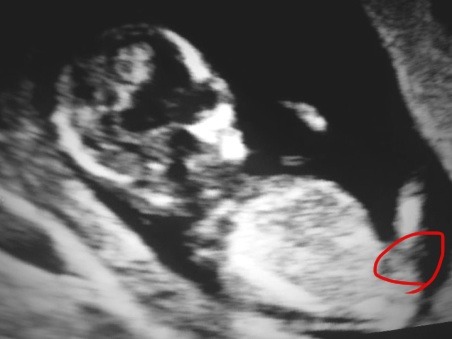

This is my friend's ultrasound- 12 weeks, 5 days. I'm posting the photo twice.....once with what I think is the nub circled....and the other without any markings so you can see better. Is this the nub? And if so, what do you think- definite boy?

Attachment 8416